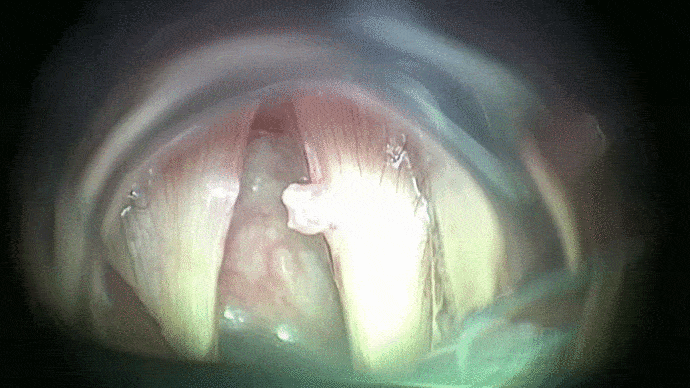

La phono-chirurgie et la micro-chirurgie laryngée est une intervention sous anesthésie générale réalisée en laryngoscopie directe en suspension et permet :

- de préciser l’extension d’une lésion laryngée

- de réaliser un prélèvement ou biopsie

- d’effectuer un geste thérapeutique laryngé pour une petite tumeur ou un polype par exemple.

L’instrumentation comporte une suspension qui libère les mains de l’opérateur. Le laryngoscope est introduit par la bouche et s’appuie sur les dents par l’intermédiaire d’une protection dentaire. Les instruments sont utilisés sous contrôle du microscope opératoire ou des optiques. Un repos vocal post opératoire vous sera dans certains cas préconisé.